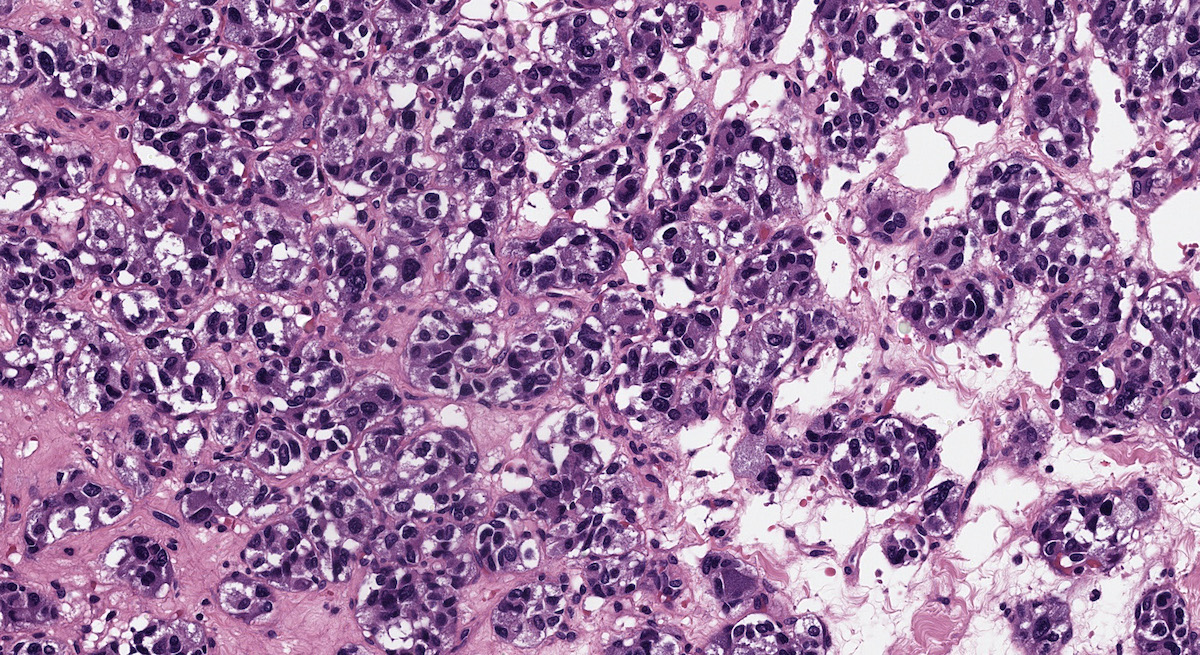

Microscopic (histologic) description

- Prevailing histologic pattern: epithelioid chief cells arranged in distinctive clusters / nests (zellballen pattern), separated by prominent fibrovascular stroma (J Clin Med 2018;7:280)

- Trabecular pattern: ribbons or cords of epithelioid cells divided by fibrous bands

- Other patterns: pseudorosette, angioma-like, spindled and sclerosing

- Chief cells: round, oval to polygonal cells with abundant granular basophilic, eosinophilic or amphophilic cytoplasm (Surg Pathol Clin 2019;12:951)

- Intracytoplasmic hyaline globules may be present in sympathoadrenal paragangliomas

- Giant multinucleated cells and bizarre cells can be present (Srp Arh Celok Lek 2002;130:7)

- Rarely, elongated and spindle shaped cells with a sarcomatoid appearance may be found

- Scattered ganglion cells can be seen

- May have nuclear atypia

- May have dysmorphic vessels, melanin-like pigment (neuromelanin) (pigmented paraganglioma), amyloid, abundant stroma and osseous metaplasia (Diagn Pathol 2012;7:77, Hum Pathol 1992;23:33)

- No or rare mitotic figures except in highly aggressive rapidly proliferating lesions

- May have focal chronic inflammatory infiltrate

- Necrosis is unusual except in patients who have undergone preoperative tumor embolization

Microscopic (histologic) images

Contributed by Luvy Delfin, M.D. and Sylvia L. Asa, M.D., Ph.D.